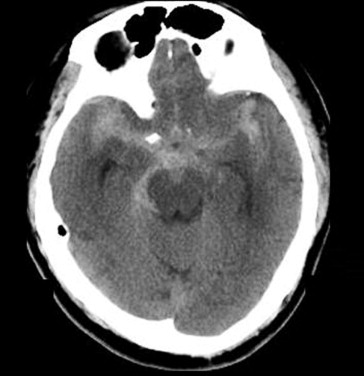

A 79-year-old hypertensive man with abrupt onset of severe headache during defecation was admitted to our hospital on January 17, 2007. There was no initial loss of consciousness, and on admission, his Glasgow Coma Scale score was 15. The patient did not have a clear history of trauma or heart disease. Headache and neck stiffness were reported by the patient but there was no obvious neurological deficit. There were no abnormalities detected with hematological and laboratory examinations, or with electrocardiography, and there were no signs of sepsis. Computed tomography (CT) performed upon admission revealed a SAH (Fig. 1), the Hunt and Hess grade for which was 2. A CT angiogram revealed segmental narrowing with diffuse atherosclerosis and segmental stenosis in the M2 segment of both branches of the MCA (Fig. 2). Angiography also identified a fusiform outpouching in the M2 segment of the right MCA. The diagnosis was of a right M2 dissecting aneurysm, but the etiology of this aneurysm was not clear.

Computer tomography scan of a diffuse subarachnoid hemorrhage over the basal ...

Figure 1.

Computer tomography scan of a diffuse subarachnoid hemorrhage over the basal cistern.